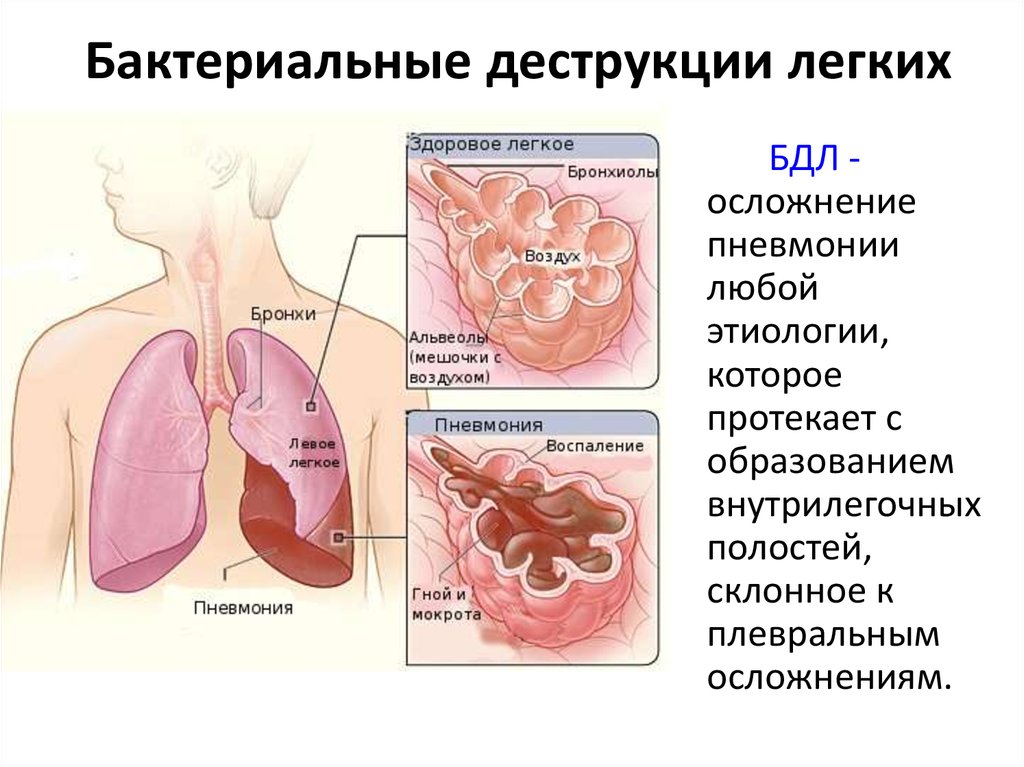

Бактериальная деструкция легких у детей презентация - 88 фото